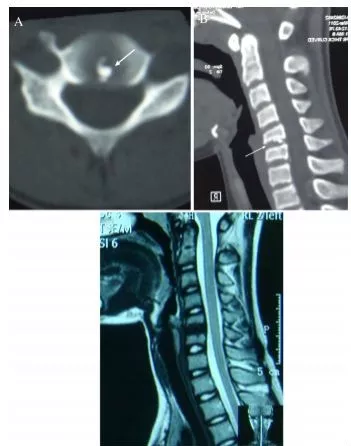

一位88歲女性患者,主訴急性頸痛伴發熱2個月入院。體溫波動在38-39.3℃,無視力模糊,無神經及脊髓壓迫徵象。頸椎CT+矢狀位重建顯示寰椎橫韌帶的曲線狀鈣化(圖A,箭頭所示),線性鈣化(圖B,箭頭所示),以及齒狀突周圍的冠狀鈣沉積(圖C,箭頭所示)。給予短期非甾體抗炎藥和潑尼松龍(15mg/d)後,其上述症狀完全緩解。同時,作者指出這類疾病通常不需要長期用藥。

一位84歲的男性患者,因“急性頸痛、僵硬伴發熱”就診。查體:頸椎向各個方向活動受限,無明顯神經病變體徵。實驗室檢查:血沉及C反應蛋白偏高。頸椎CT平掃提示齒狀突橫韌帶鈣化(箭頭所示),從而診斷為齒狀突加冠綜合徵。給予洛索洛芬治療一週後,上述症狀完全緩解,而且炎性指標恢復正常。

患者女,76歲。無明顯誘因下出現頸部疼痛、僵硬伴發熱 3 d 入院 ,頸部疼痛呈間歇性,頸痛視覺模擬評分(VAS)為7分,體溫37.7~38.8℃,無四肢疼痛麻木,無行走不穩,二便正常。既往無痛風、類風溼關節炎病史。入院體檢:頸椎旋轉明顯受限,頸部肌肉僵硬,未查及明顯神經或脊髓損傷體徵。實驗室檢查:白細胞11.2×109/L,紅細胞沉降率35.4 mm/h,超敏C反應蛋白14.7 mg/L,類風溼因子及降鈣素原正常。頸椎CT平掃示齒狀突後側寰椎橫韌帶弧形鈣化(左圖箭頭)和豎直線樣鈣化(右圖箭頭)。依據患者病史、體徵及輔助檢查,齒狀突加冠綜合徵可基本診斷。入院後給予氯諾昔康 8 mg靜脈滴注每日2次,地塞米松起始量10 mg靜脈滴注每日1次,3日後改為5mg/d。連續治療5 d後,患者入院時症狀明顯緩解,複查白細胞、紅細胞沉降率、超敏C反應蛋白均恢復正常。隨訪半年,未有頸痛伴發熱症狀出現。